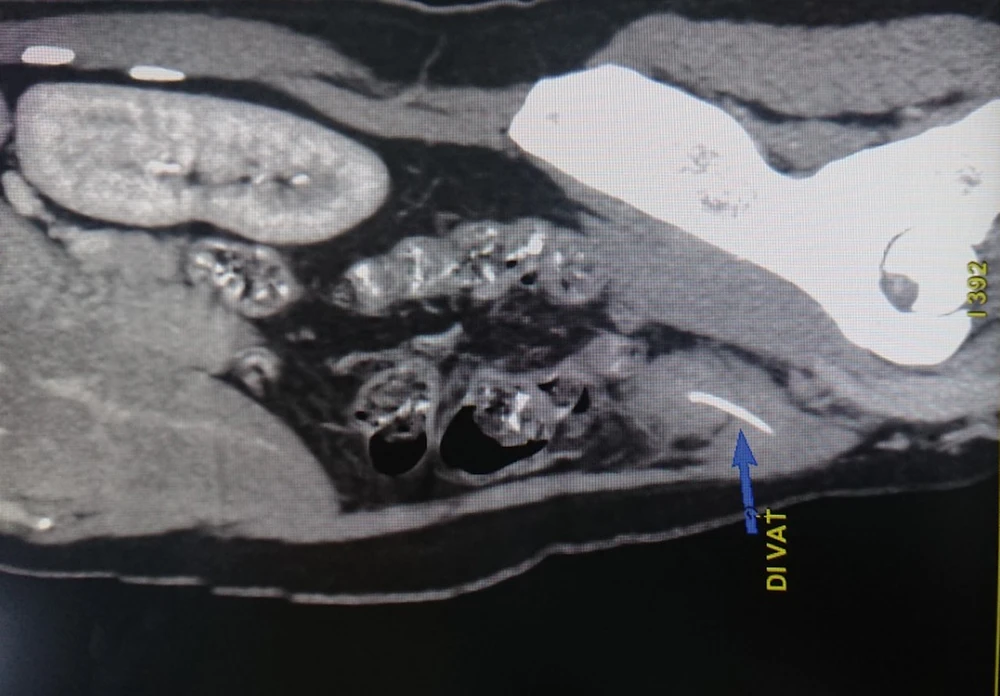

Hình ảnh xương cá dài 3 cm đâm xuyên ruột bệnh nhân. Ảnh: HD

Kết quả chụp CT bụng có cản quang cho thấy có dị vật dạng xương cá đâm xuyên thành quai ruột non vùng hố chậu trái. Các bác sĩ đã phẫu thuật nội soi cấp cứu cho bệnh nhân, bóc tách khối viêm ở thành bụng thì thấy hố chậu trái có khối viêm kích thước 3x4 cm được mạc nối lớn bám.